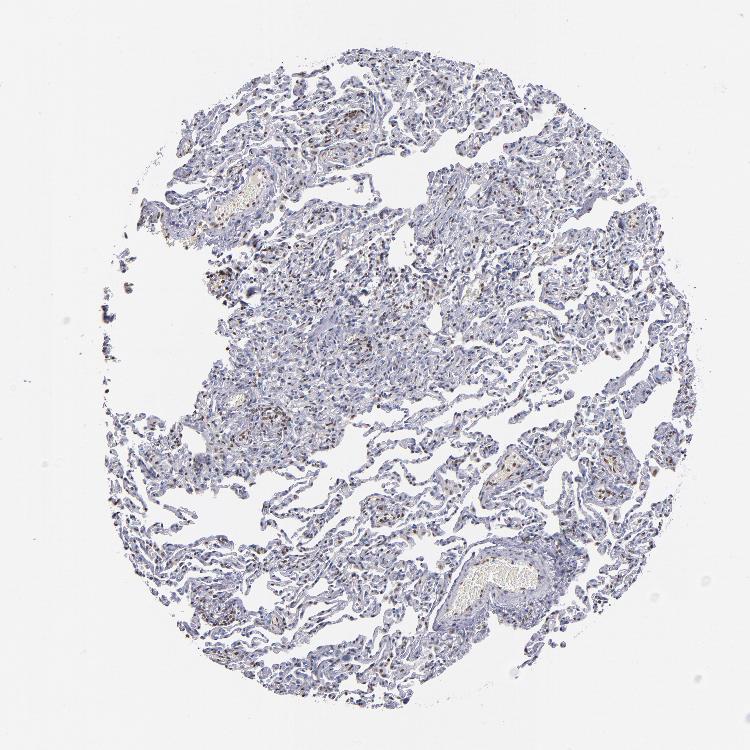

IFI16